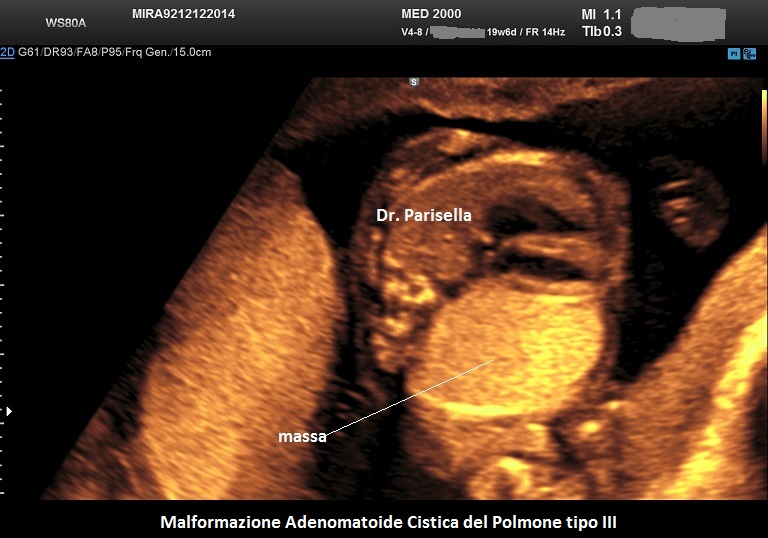

MACP tipo III: è una massa solida che contiene cisti molto piccole < 0,5 cm.

. Il tipo III è una massa solida che contiene cisti molto piccole (< 5,0 mm). (Rolo LC et al., 2022).

Si presenta come una massa occupante spazio di solito unilaterale in più del 95% dei casi e solitamente coinvolge un lobo o segmento del polmone; nella sua evoluzione determina dislocazione del mediastino e del cuore. L'ecostruttura distingue due forme: una forma multicistica  caratterizzata dalla presenza di multiple cisti di varia grandezza (tipo I e II) e una forma microcistica (tipo III) corrispondente alla variante solida.